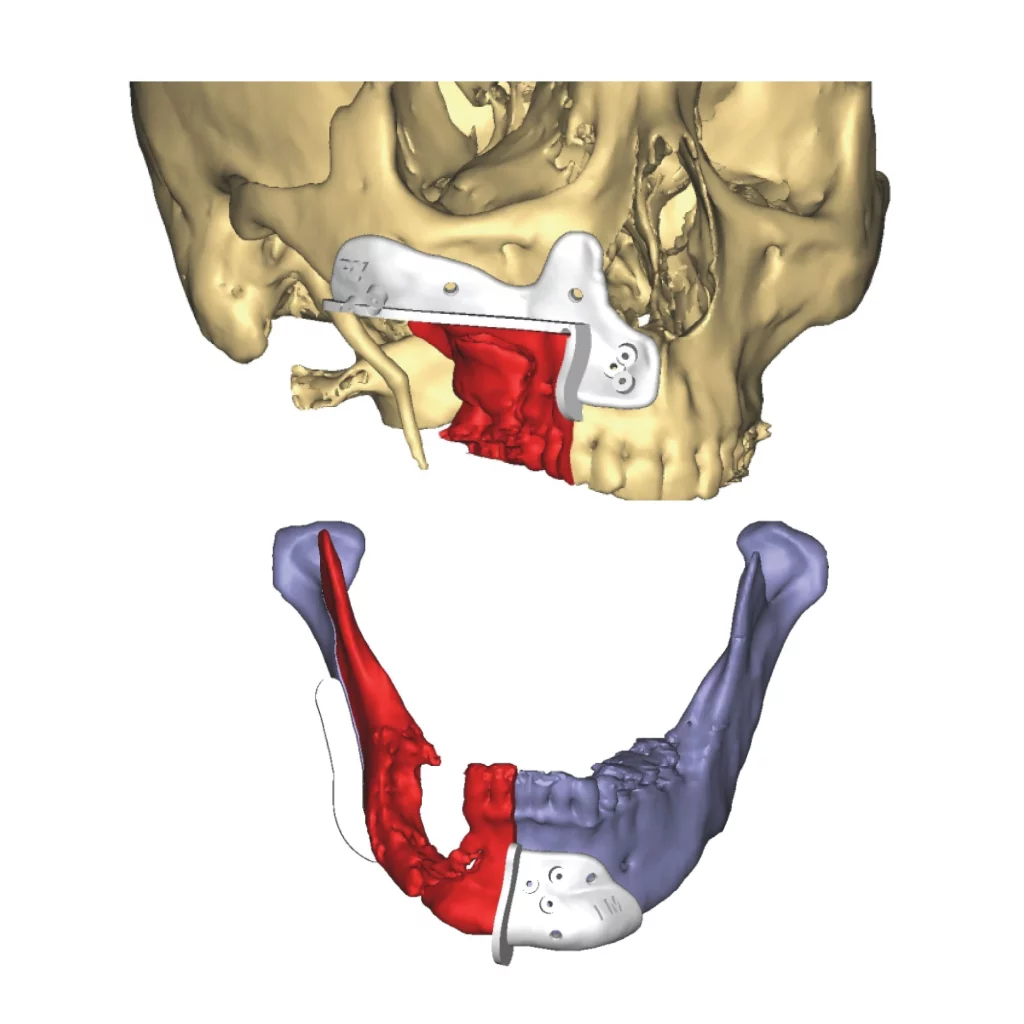

Guias de osteotomia personalizados

Os Guias de osteotomia personalizados são dispositivos indicados para procedimentos cirúrgicos craniomaxilofaciais planejados e possuem a finalidade de transferir um plano pré-operatório para a cirurgia. Eles orientam e/ou auxiliam o cirurgião a realizar osteotomias, furações e marcações no osso conforme o planejamento pré-operatório, incluindo a implantação de produtos customizados ou standard determinando a posição destes em procedimentos cirúrgicos craniomaxilofaciais, como por exemplo, cirurgias ortognáticas e reconstruções.

- Fabricados em poliamida

- Altíssima precisão, fornecendo uma adaptação à anatomia do paciente

- Modelos para osteotomia Lefort, osteotomia e posicionamento de mento, osteotomia mandibular e maxilar, extração de enxerto para cirurgia de reconstrução microvascularizada, ostetomia e posicionamente craniano